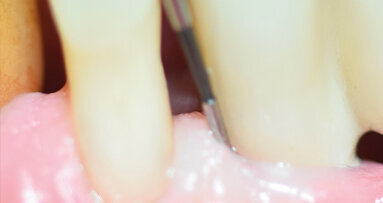

Le tecniche non chirurgiche richiedono la completa rimozione del vecchio materiale da otturazione presente nello spazio endodontico al fine di ottenere una sagomatura, disinfezione e otturazione tridimensionale del sistema canalare più profonda e completa: condizioni indispensabili per ottenere il successo3 (Figg. 1b, 1c).